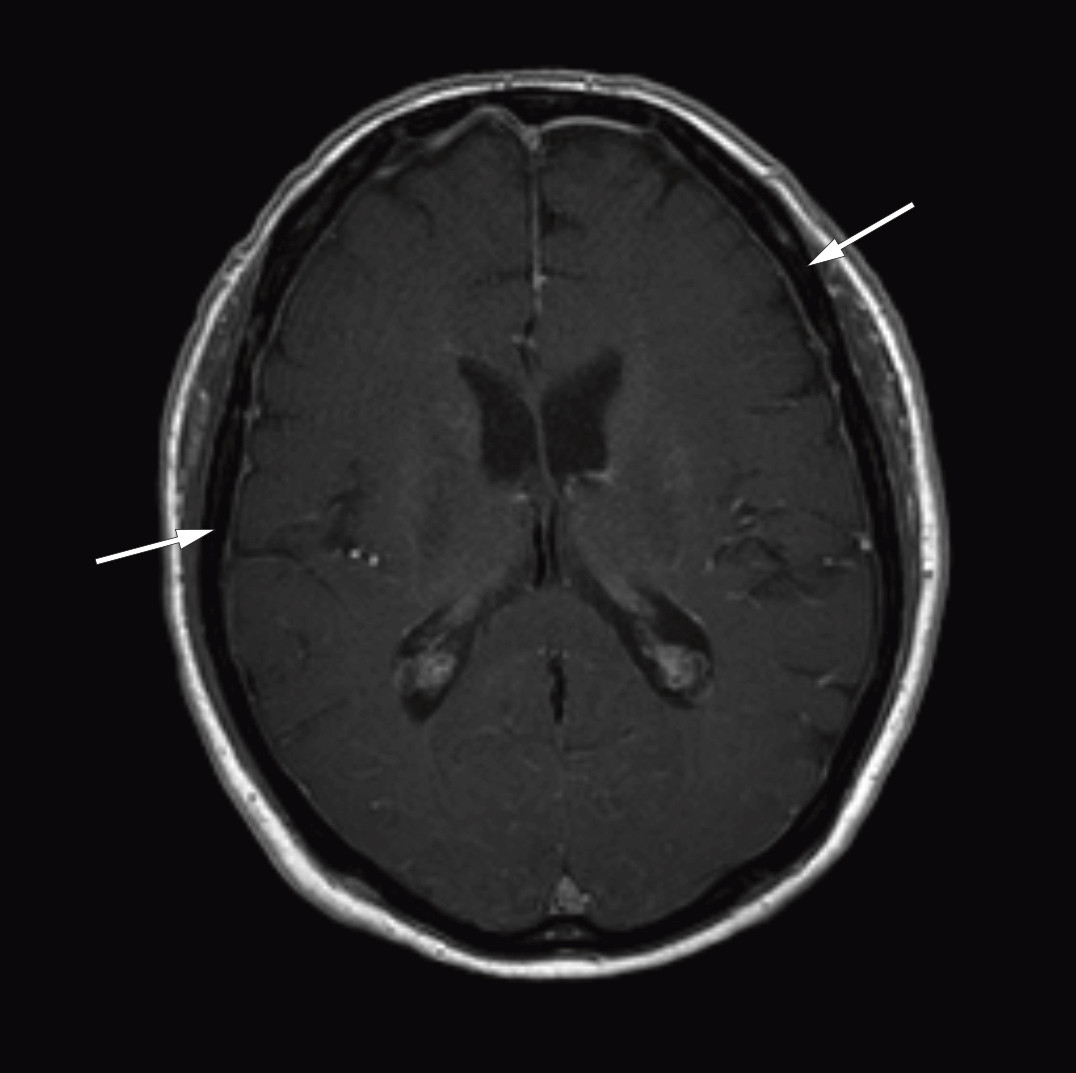

Etter at diagnosen Bing-Neel-syndrom var stilt, gransket vi MR-bildene av cerebrum og lumbosakralcolumna på ny og fant patologisk fortykkede og kontrastladende meninger over begge storhjernehemisfærer (figur 1) og cerebellum samt bølgede og fortykkede cauda equina-røtter (figur 2). Vi konkluderte med at de fortykkede meningene var uttrykk for diffus affeksjon av sentralnervesystemet forenlig med Bing-Neel-syndrom. Funnet av fortykkede cauda equina-røtter ble også antatt å ha sammenheng med syndromet, men det kunne ikke fastslås med sikkerhet siden forandringene var sparsomme, og bildene dessverre ble tatt uten kontrast.